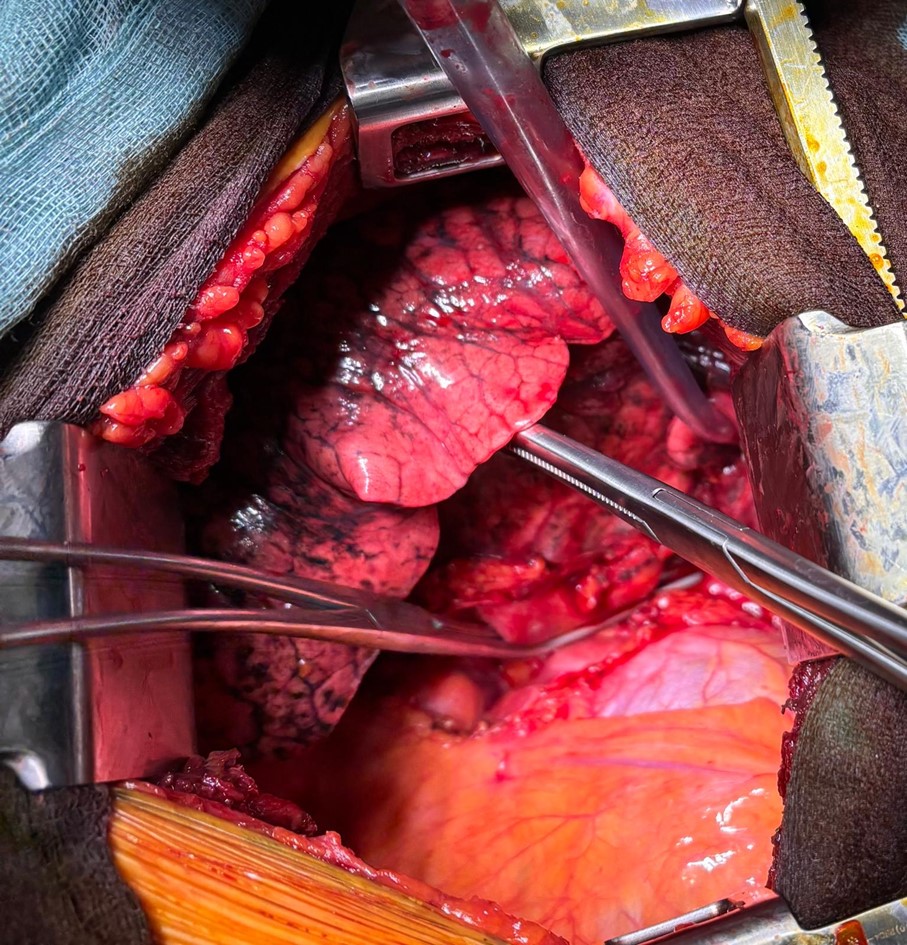

Surgical treatment of Locally Advanced Lung tumors after induction chemo-immunotherapy

Locally advanced primary lung cancers (Stages IIb-IIIa) account for approximately 30% of new diagnoses per year. The correct indication for their treatment has been the subject of controversy among oncologists, radiotherapists and thoracic surgeons for years. Recent developments in oncology, with the introduction of clinical trials involving immunotherapy drugs, have undoubtedly increased the treatment options for these neoplasms, increasingly involving surgeons in order to improve clinical response and patient survival.

In multidisciplinary clinical discussions for these tumours, important new insights are coming up: a) the importance of proper clinical/invasive staging of the tumour; b) rethinking the idea of surgical resectability of the lesion (a judgement that should only be made by the thoracic surgeon); c) the assessment of resectability (the ability to achieve radical oncological resection) and the patient’s operability (the ability to tolerate surgery and overcome any post-operative complications).Surgery after chemo-immunotherapy is very complex and requires significant expertise.

The cause of this technical complexity is linked to the profound tissue alterations induced by cancer treatment (and in particular by immunotherapy). There are few centres in Italy and Europe capable of performing this type of surgery. Over the last year, thanks to close collaboration with oncologists, the Thoracic Surgery Unit has performed 14 surgical procedures on patients treated with induction chemo-immunotherapy. This series, achieved in such a short time, places it among the most important Italian units.

From a surgical point of view, these are extremely complex surgical procedures due to the direct effects of radiotherapy and immunotherapy, which effectively disrupt the hilar structures, causing profound tissue alterations. At the same time, the surgical procedures are anatomically very extensive and complex, involving large amounts of tissue resection, with extended pneumonectomy being the most common. The post-operative course of these patients is also often complex, due to the possible development of complications, among which respiratory ones are the most serious and threatening.